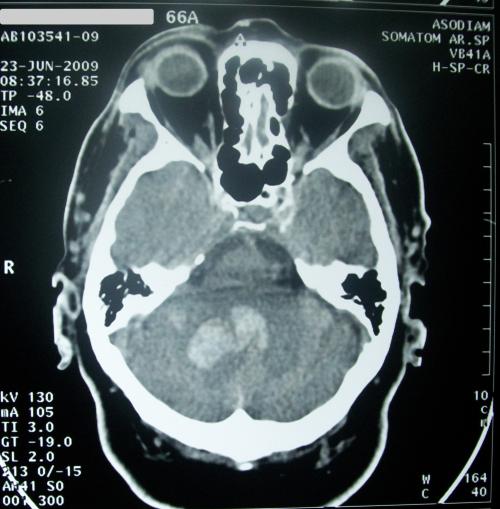

TAC que muestra un caso de accidente cerebrovascular hemorrágico. (Foto: DICYT)